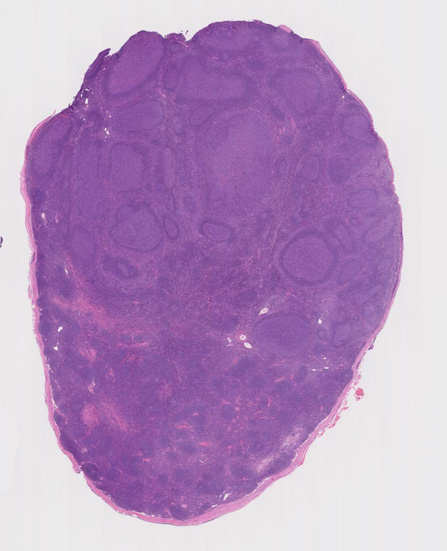

大きな胚中心を持つ多数のリンパ濾胞が見られる。胚中心の辺縁は不明瞭でマントル層も薄くなっている。1カ所マントル層リンパ球の侵入によりバラバラになった巨大な胚中心が認められ, macrofollicular patternと記載されるPTGCです。

鑑別にあがるfollicular lymphoma floral variantは全ての濾胞が腫瘍性であり, 本性例では除外可能と考える。

Diagnosis: Reactive lymphadenitis with PTGC